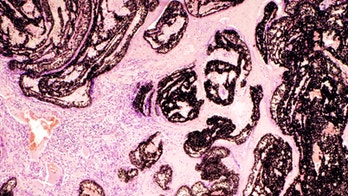

October 24, 2015 Astronomy algorithms help detect aggressive cancers Cancer researchers are teaming up with astronomers using computerized algorithms designed for viewing distant galaxies to spot biomarkers that can indicate the aggressiveness of a tumor